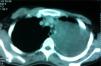

Case ReportA 19-year-old patient was admitted to our hospital for pain in the left arm. She presented no other symptoms. Both the physical examination and anamnesis were anodyne. Plain chest radiography revealed an extensive opacity that occupied almost the entire left hemithorax and caused a deviation of the trachea and the mediastinum towards the right (Fig. 1). Afterwards, computed tomography (CT) exploration better defined this lesion and revealed a solid heterogeneous mass that measured 16cm×15cm×15cm (Fig. 2). The mass extended to the left supraclavicular region, with no skeletal destruction. It was characterized by smooth edges and it demonstrated a direct relationship with the mediastinal vascular structures, without obliterating them. The left lung was completely collapsed. After CT, the patient underwent magnetic resonance imaging (MRI) for more detailed evaluation. The mass originated at the posterior mediastinum, where it manifested low signal intensity in T1 and high signal intensity that was heterogeneous in the weighted MR images in T2, and, after the administration of gadolinium (0,1mmol/kg), an intense contrast was demonstrated. We considered that the lesion may possibly have been a lymphoma or, although less likely, a primary lung carcinoma as an initial diagnosis. Positron emission tomography –computed tomography (PET-CT) was ordered, which revealed increased fluorodeoxyglucose (18FFDG) uptake by the mass. For the definitive diagnosis, a biopsy was taken by CT-guided transthoracic needle aspiration. The histopathologic exam revealed layers of small, round, blue cells with small round nuclei and limited cytoplasm. Immunohistochemistry demonstrated positive staining for CD99 and vimentin. It was negative for all lymphoma markers, including CD31, CD34, CD45, desmin and cytokeratins. Given these findings, the mass was diagnosed as an EES. Immediately afterwards, we consulted with the thoracic surgery department and an intervention was programmed to resect the lesion.